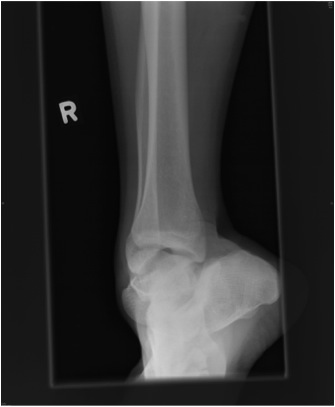

Knee

Approaches

Medial Parapatellar

Medial

Lateral

Posterior

Modified Posterior

Medial Parapatellar Approach

Indications

Synovectomy

Patellectomy

TKR

Technique